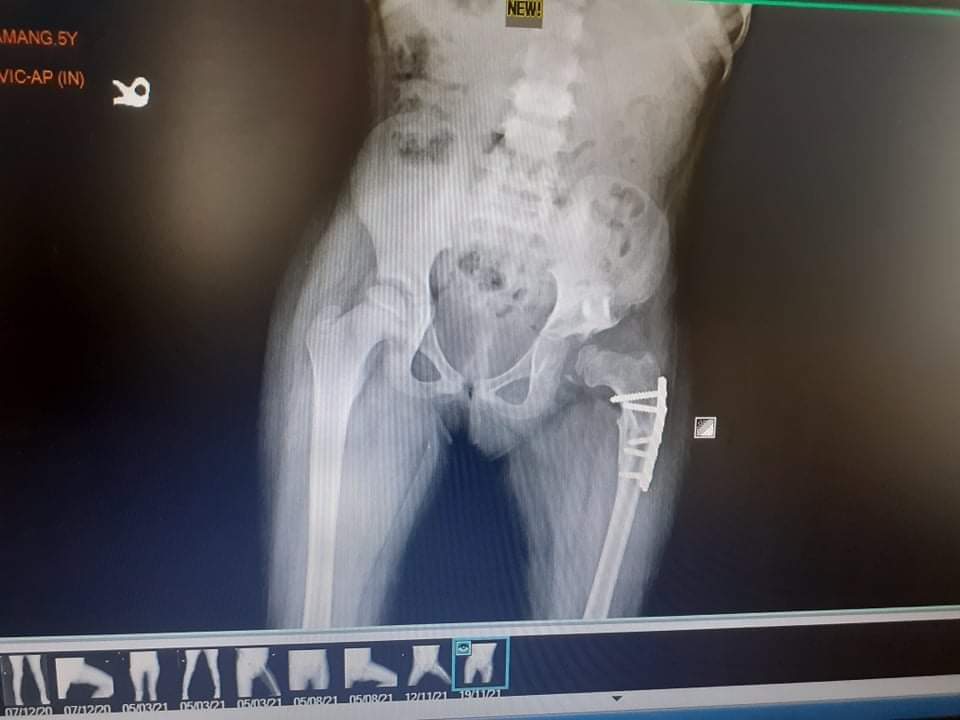

L’ Association Manoj a pris en charge l’opération d’une nouvelle (jeune) patiente. Il s’agit de Yangsang Tamang âgée de 6 ans. Dhan l’avait découverte le 28 novembre 2020, soit un an auparavant, dans le village de Namki, près de Bachchek (VDC de Simjung). Elle a été soignée pour un problème au fémur, résultant d’une fracture ou d’une malformation congénitale. Nous lui souhaitons un bon rétablissement et espérons que l’opération pourra la soulager.